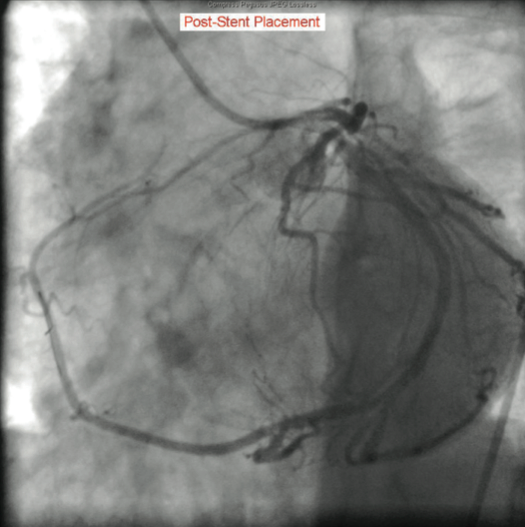

The catheterization and angiogram showed a patent left main coronary artery that bifurcated into the left anterior descending (LAD) and the left circumflex (LCX). The LAD had a mid 50% stenosis and the LCX was a large-sized vessel that gave off three obtuse marginal (OM) branches and continued distally into the right

side of the heart, filling the right coronary artery (RCA) from the distal end retrograde. The LCX had a mid 70-80% lesion that was confirmed by intravascular ultrasound (IVUS). The right coronary artery had no ostium and received retrograde filling via the LCX, continuing distally into the right myocardium. The LCX 80% mid stenosis was successfully revascularized with deployment of two drug-eluting stents. The patient was placed on post-procedure clopidogrel, simvastatin, beta blockers, and nitroglycerin.